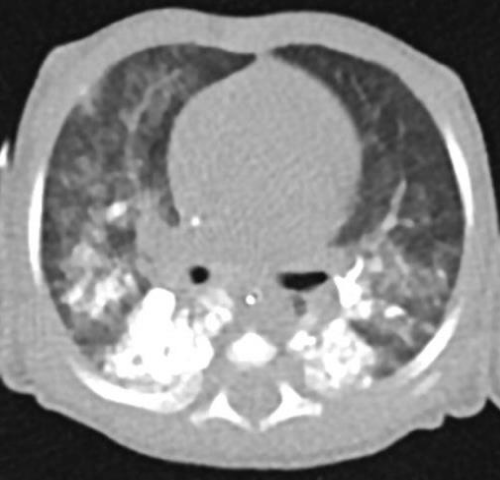

The infant had re-applied to the external center one week later with increase of the sputum, saliva, cough and vomiting. The computed thoracic tomography showed that dense radioopacity especially in both lower lobes of the lungs. It was compatible with the barium contrast material aspirated in the pharyngoesophageal examination which was performed a month earlier (Figure 3). It was also observed that focal ground glass densities were present in the lower, middle lobe of the right lung, the lower lobe of the left lung which had depended to aspiration pneumonia by our colleagues. The chest X-ray had taken a few days after aspiration that had been similarly images (Figure 4).

Figure 3: Unenhanced thoracic CT: diffuse patch opacity, particularly in the lower lobe posterior segments of both lung parenchyma. The lung parenchyma areas have ground glass densities.